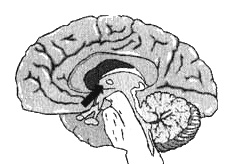

Уилли рассказал мне о двух ДТП и о том, как резко изменился его характер. Я немедленно назначил SPECT. Результаты подтвердили мои опасения. В двух областях обнаружилась повышенная активность — они работали с большой перегрузкой. Одна находилась в левой височной доле, где нарушение функций часто связано с паранойей и насилием. Другая располагалась в верхней средней части фронтальных долей (поясная зона) в той части мозга, которая отвечает за переключение внимания с одного объекта на другой. Когда гиперактивность наблюдается в этой зоне, человек не может переключиться, и мысль его начинает двигаться по спирали. Как только я увидел снимки мозга Уилли, то сразу понял, чем были вызваны все изменения: паранойя, вспыльчивость и негативные мысли о соседе по комнате, от которых он никак не мог отделаться.

Мозг Уилли — травма головы

Иллюстрация к книге — Измените свой мозг - изменится и жизнь! [i_028.jpg]

Трехмерное изображение — активный мозг, вид сбоку. Обратите внимание на выраженное повышение активности в поясной системе и в левой височной доле (см. стрелки).